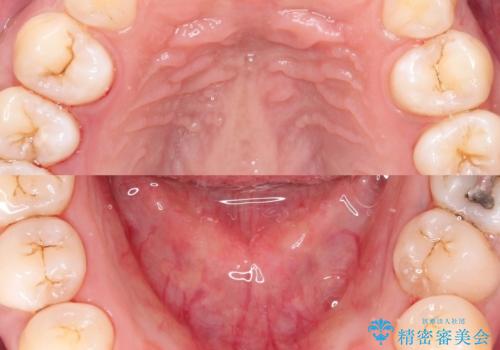

歯科衛生士による、歯石や着色除去の前後写真です。

- 毎日の喫煙による着色を気にして来院されました。前歯から奥歯まで広い範囲で着色が認められたため、歯科衛生士による専門的な機械を使用したPMTC(自費クリーニング)を行いました。